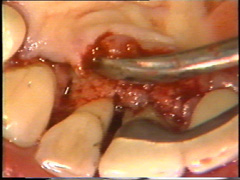

Las superficies de la raíz se limpian

(raspado y alisado radicular) cuidadosamente y el tejido de granulación en los

defectos óseos (cráter) es eliminado. En la superficie bucal del segundo premolar hay

un cráter óseo y cálculo en la supericies dental adyacente.

El cálculo del segundo premolar

está unido firmemente a la superficie dental y es un proceso tedioso el

quitarlo.